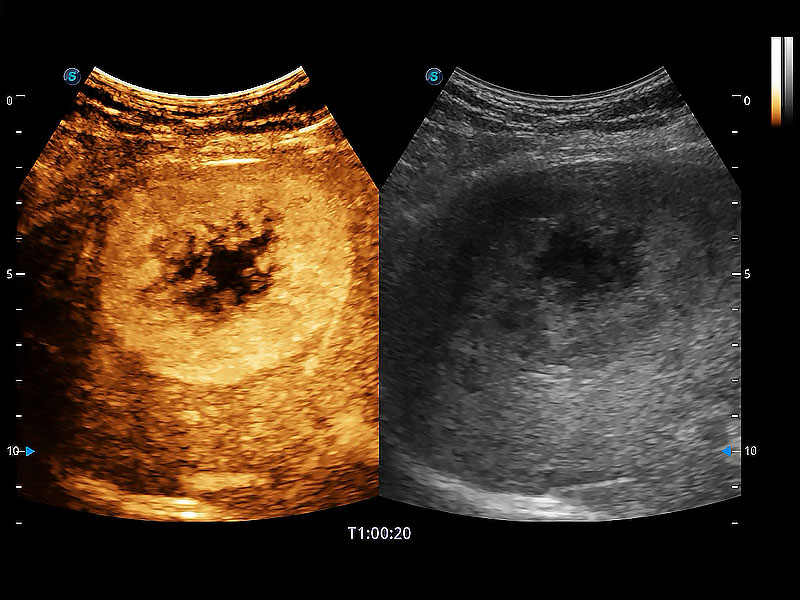

在傳統(tǒng)二維血流成像的基礎(chǔ)上,呈現(xiàn)血流的立體感,具有動感的生命力之美。即便是微小的血管也能輕松應(yīng)對,提高了血流的視覺敏感性。

非線性融合造影成像充分利用諧波和基波信號,為難以觀察的血流進(jìn)行增強(qiáng)顯像??捎糜诰€陣、凸陣、微凸陣、相控陣探頭。